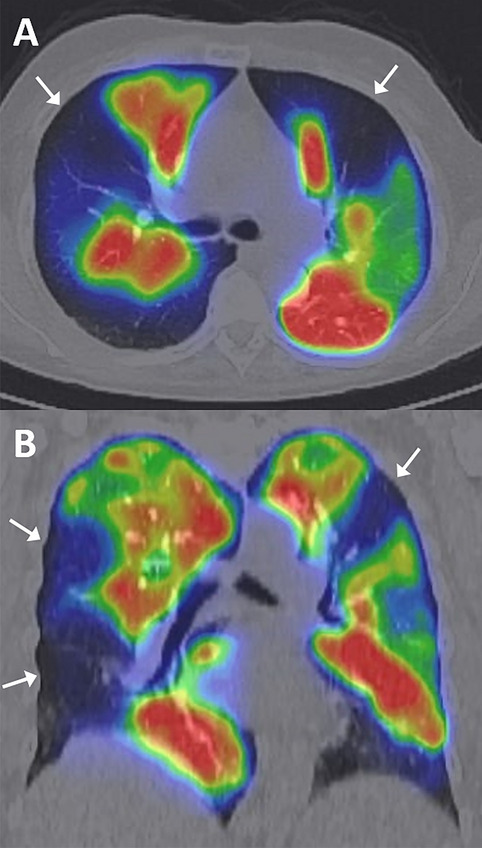

Immagini di fusione SPECT/TC perfusionale di un paziente con ipertensione polmonare tromboembolica cronica (CTEPH).

Le sezioni assiali (A) e coronali (B) mostrano multipli difetti di perfusione segmentali, in particolare nelle regioni periferiche di entrambi i polmoni (frecce bianche). Questi reperti sono caratteristici della CTEPH.